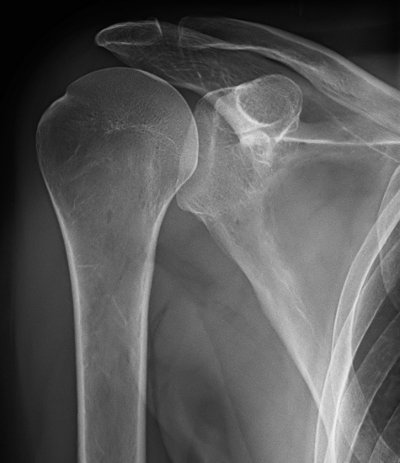

Behandlungsbeispiel

Die Orthovolttherapie ist eine schmerzfreie, nichtinvasive Behandlung mit speziellen energetischen Röntgenstrahlen.